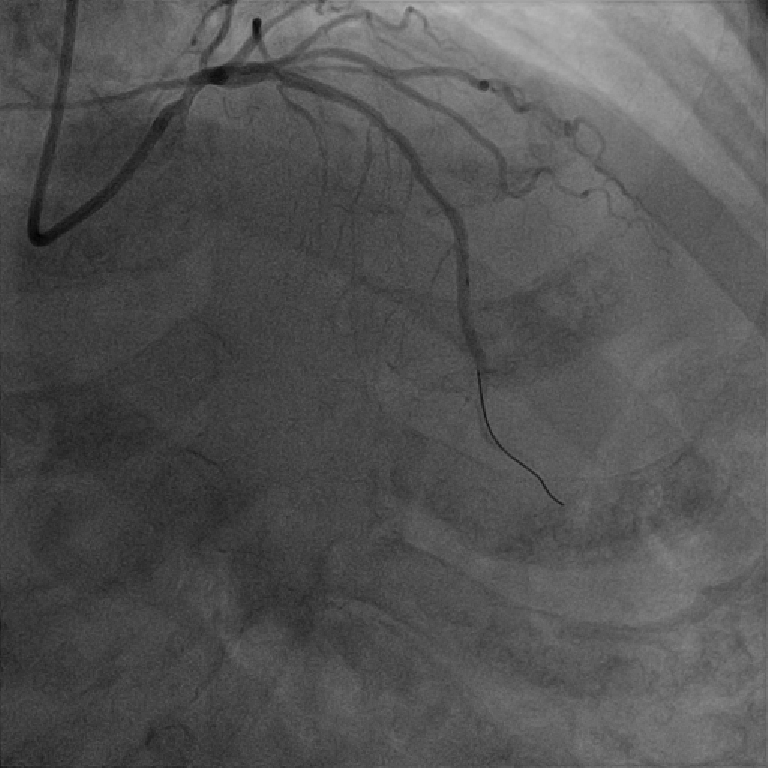

1,过导丝,通过病变,行IVUS

2,由远至近IVUS评估,不同切面对应不同面积,提示左主干面积4~5mm²,属于重度狭窄,需要介入治疗。

3,担心guiding深插对开口2次损伤,放窦外导丝进一步保护,根据ivus指导,植入4.0x18mm 支架。

4,不同体位确定开口位置,释放支架。

介入经过——最后影像

7,给与4.0x15mm非顺应性球囊进行高压后扩张,压力维持在16~20atm。最后检查血管影像。